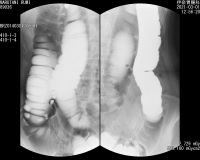

*直腸全摘手術前のレントゲン写真 (伊奈胃腸病院)

2021 3.22 直腸手術